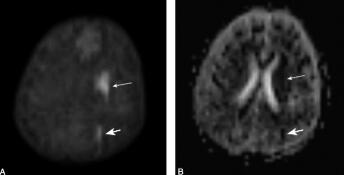

第三次头颅DWI及MRI增强扫描(6月20日):左顶、枕叶及左基底节区、放射冠、半卵圆中心多发斑片状异常信号灶增强后均未见明显强化,性质待定,不除外脑梗死。DWI示左侧基底节区、放射冠、半卵圆中心见片状高信号影,左顶枕叶亦见脑回样高信号影(图3),左侧基底节区、放射冠、半卵圆中心及左顶枕叶病灶表观弥散系数(apparent diffusion coefficient,ADC)值减低,考虑脑梗死可能性大。

图3 2011年6月20日行DWI;A.图像上左侧尾状核处(细箭头)及左顶叶处(粗箭头)可见明显高信号影;B.ADC示上述病灶均为低信号